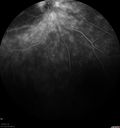

FLUORESCEIN ANGIOGRAPHY: Fluorescein angiography shows hyperfluorescence in a pattern consistent with retinitis pigmentosa variance, where there is sparing of the central macula with increased hyperfluorescence in the periphery.